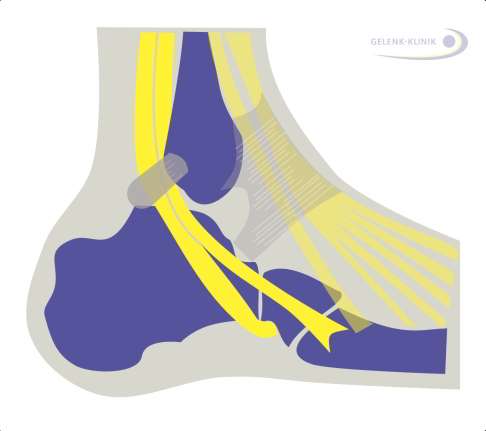

Schäden an der Peronealsehne

Häufig verursacht eine Hohlfußfehlstellung Schäden an den äußeren Sehnen, den sog. Peronealsehnen. Die Peronealsehnen kontrollieren die Fußposition beim Gehen und sind für das Absenken des Fußes (Plantarflexion) sowie für die horizontale Außenrotation des Fußes zuständig. Daher finden sich in jedem Bein zwei solcher Sehnen.

Chronische Entzündungen der Sehnen sind häufig auf den Hohlfuß zurückzuführen. Dabei können auch Teilschäden resultieren. Diese haben wegen der unterschiedlichen Funktion der beiden Peronealmuskeln (Wadenmuskeln), welche durch die Sehnen mit dem Fuß verbunden werden, sehr weitreichende Folgen. Schädigungen der Peronealsehnen führen daher zur Störung der Fußmotorik.

Für den Hohlfuß ist eine andere Sehne verantwortlich: Wenn die Peronaeus-longus-Sehne einen stärkeren Zug ausübt als die Tibialis-anterior-Sehne, wird der erste Zehenstrahl nach unten gedrückt und das Fußlängsgewölbe hebt sich an.